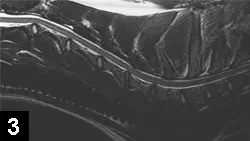

MRI of the cervical spine disclosed dorsal and ventral compression of the spinal cord at the level of the C5-C6 disk space (Figure 3).

Figure 3. Sagittal cervical spinal MRI showing dorsal and ventral compression of the spinal cord at the C5-C6 disk space.